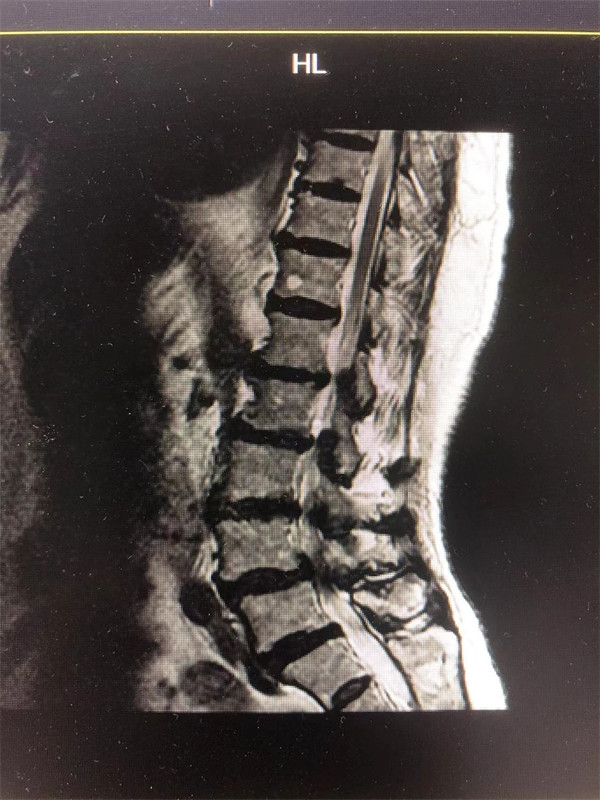

手術(shù)前↓

戈主任仔細詢問阿婆病情癥狀,綜合查體及MRI片情況,認為阿婆有明顯的腰椎滑脫,腰椎管狹窄,這是引發(fā)阿婆病痛的主要因素。

阿婆曾在院外多家醫(yī)院就醫(yī),被診斷為腰4椎體滑脫癥、腰椎管狹窄癥、腰椎間盤突出癥,外院予以止痛、理療、針灸等各種保守方式治療,病情未見明顯改善。